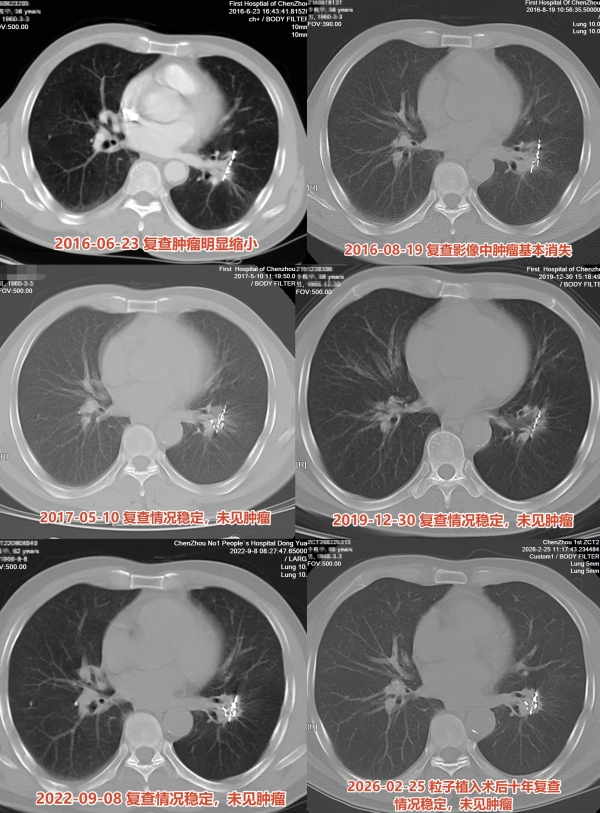

三个月后,几乎消失:pCR(临床缓解)

2016年8月19日,术后不到三个月,复查CT结果出来了:原本边界不清、占据左肺下叶的肿块,几乎消失殆尽,以及那些已失去放射活性、静静留存的金属粒子。

医学上,这被称为临床完全缓解。

此后,李伯伯每隔几年随访复查CT,影像持续保持干净、无进展的状态。

一年、两年、五年……

直到2026年的今天,再次复查:术后十年,没有复发,没有进展。